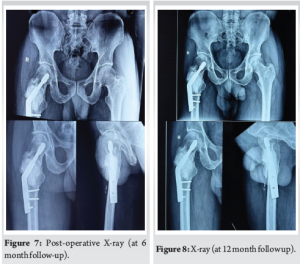

The first re-examination was started in the 1st month after surgery, and follow-ups were conducted at 2 months, 4 months, 6 months (Fig. 7), and 12 months (Fig. 8). The follow-up examinations included local X-rays, surgical site inspection, and range of motion.